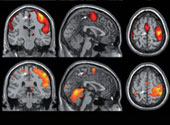

Locurile exacte ce corespund vaginului, colului uterin şi mameloanelor femeilor pe cortexul senzorial al creierului au fost „cartografiate” pentru prima dată, dovedind că stimularea vaginală activează regiuni diferite ale creierului de cele activate prin stimularea clitorisului. Studiul a constatat, de asemenea, o legătură directă între mameloane şi organele genitale, ceea ce poate explica de ce unele femei pot avea orgasm doar prin stimularea mameloanelor. Descoperirile ar putea ajuta femeile care au suferit leziuni ale nervilor la naştere sau pe timpul unor boli.

Până recent, nimeni nu ştia cu siguranţă ce se întâmplă la nivelul creierului femeii în timpul actului sexual. Scanarea creierului arată în prezent faptul că stimularea diferitelor regiuni erogene activează zone diferite.

Acest lucru s-a schimbat anul trecut, când o echipă condusă de Lars Michels de la Spitalul Universitar pentru Copii din Zurich, Elveţia, au folosit imagistica prin rezonanţă magnetică funcţională pentru a confirma faptul că poziţia clitorisului pe homunculus se află aproximativ în aceeaşi poziţie cu penisul la bărbaţi. Barry Komisaruk de la Rutgers University din Newark, New Jersey şi colegii săi au folosit acum aceeaşi metodă pentru a cartografia poziţia clitorisului, a vaginului şi a colului uterin pe cortexul senzorial pe măsură ce femeile s-au autostimulat.

"Aceasta este o dovadă puternică că există o diferenţă mare între aceste regiuni diferite", spune Stuart Brody de la Universitatea de Vest din Scoţia în Paisley, Marea Britanie, unul dintre cercetătorii implicaţi în studiu. Unii au susţinut că femeile care obţin plăcere prin stimularea vaginală, fac acest lucru deoarece clitorisul lor este stimulat în mod indirect, dar rezultatele actuale contrazic acest lucru. "Acestea susţin rapoartele femeilor care experimentează orgasmul la diferite forme de stimulare", spune Beverly Whipple, de asemenea, de la Universitatea Rutgers, care nu a fost implicată în studiu.